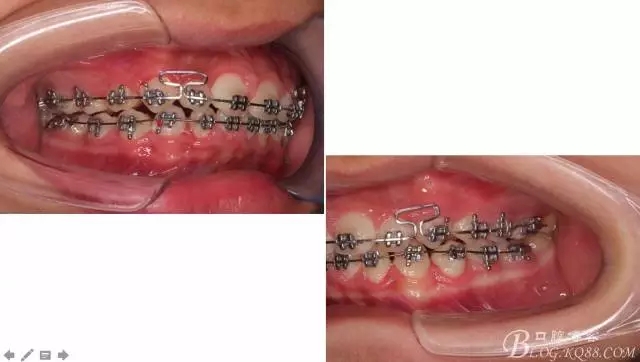

看看口內(nèi)照吧!真象“大暴牙”v假象“大暴牙”

三度深覆合,三度深覆蓋,尖牙,磨牙均二類關(guān)系!